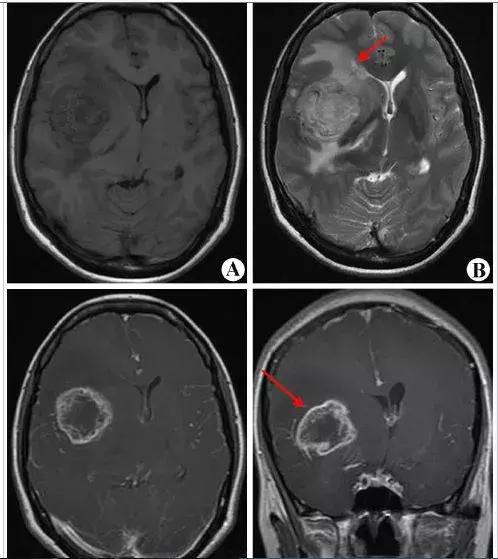

结果发现,常规手机使用并不是脑瘤的危险因素,然而,总体累计特异性能量(TCSE, J/kg)最高的20%人群中(TCSE>3123.9 J/kg),手机使用7年以上者,胶质瘤风险增加1.91倍,脑膜瘤风险增加2.01倍。

在发生部位上,在使用手机10年以上人群中,手机辐射最集中的区域(耳周)发生胶质瘤的风险增加2.8倍。